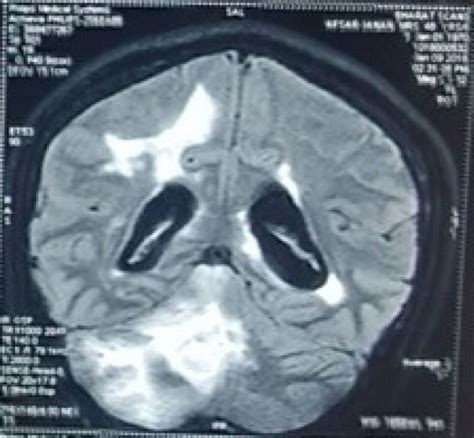

So, what’s the deal with tumefactive MS ? Imagine multiple sclerosis, but with some major league players on the field. Typically, MS lesions are smaller, scattered throughout the brain and spinal cord. Tumefactive MS, on the other hand, is characterized by large demyelinating lesions, usually bigger than 2 centimeters in diameter. These lesions can appear in various parts of the central nervous system, but they often show up in the white matter of the cerebral hemispheres. Because of their size and appearance on imaging scans like an MRI, they can sometimes be mistaken for brain tumors, hence the “tumefactive” part of the name, meaning “tumor-like.” This can lead to diagnostic challenges and, understandably, a lot of anxiety for patients and their families. It’s a more aggressive presentation of MS, and the symptoms can be quite dramatic, often appearing suddenly and severely. These symptoms vary depending on the location of the lesion, but can include things like weakness, sensory changes, vision problems, and cognitive difficulties. Understanding this distinction is vital because the management approach for tumefactive MS differs from typical MS. We’re talking about a condition that requires prompt attention and a tailored treatment plan. It’s not just about slowing down the disease; it’s often about actively managing the acute, inflammatory phase of these large lesions. The impact on daily life can be significant, making early and accurate diagnosis absolutely paramount. We’ll delve deeper into the diagnostic process shortly, but for now, know that tumefactive MS is a distinct and serious form of the disease that necessitates specialized care.

Getting a solid diagnosis for tumefactive MS can be a bit of a puzzle, guys. It’s not as straightforward as spotting a few small dots on an MRI. The hallmark of tumefactive MS is those big, scary-looking lesions we talked about, often appearing as solitary or multiple large lesions on magnetic resonance imaging (MRI). However, the challenge is that these lesions can mimic other serious conditions, most notably brain tumors or other inflammatory diseases. This is why a comprehensive diagnostic approach is absolutely critical . Doctors don’t just rely on one piece of the puzzle. They’ll look at your medical history, perform a thorough neurological examination, and then dive into advanced imaging. MRI with contrast is key here, as it helps to highlight active inflammation within the lesions. Sometimes, advanced MRI techniques like diffusion-weighted imaging (DWI) or susceptibility-weighted imaging (SWI) can provide additional clues to help differentiate between MS lesions and tumors. But it doesn’t stop there. To further rule out other possibilities and confirm an MS diagnosis, doctors might also order a lumbar puncture (spinal tap) to analyze the cerebrospinal fluid (CSF) for specific antibodies, known as oligoclonal bands, which are often present in MS. Evoked potential tests, which measure the electrical activity in the brain in response to sensory stimuli, can also provide evidence of demyelination. In some tricky cases, where the diagnosis remains uncertain despite all these tests, a brain biopsy might be considered. This is a more invasive procedure, but it can provide a definitive diagnosis by examining a small sample of brain tissue under a microscope. The key takeaway here is that diagnosing tumefactive MS is a multi-faceted process . It requires the expertise of neurologists, neuroradiologists, and sometimes even neurosurgeons. The goal is always to be as accurate and as quick as possible, because the sooner we nail down the diagnosis, the sooner we can start the right treatment and improve outcomes. It’s a journey that requires patience and trust in your medical team, and understanding the steps involved can help alleviate some of the uncertainty.